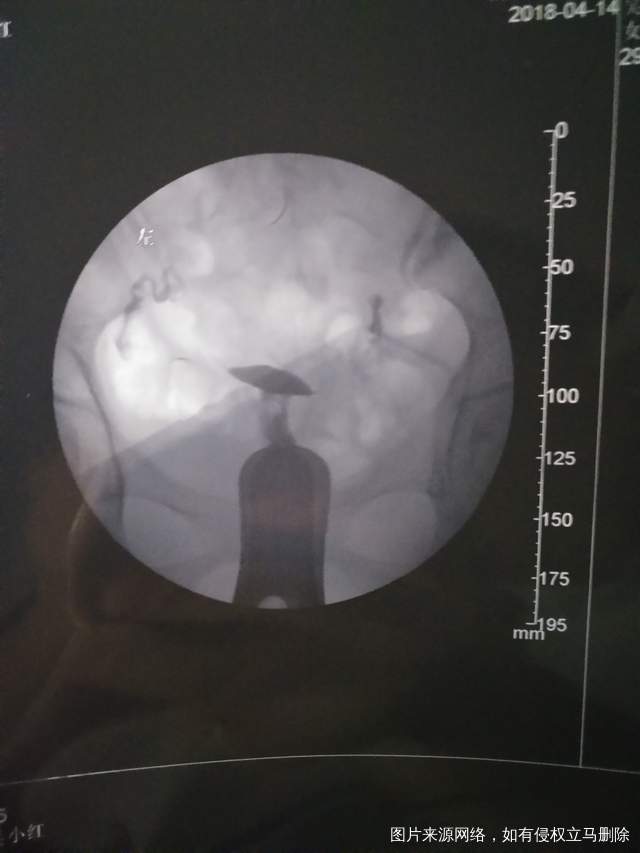

医生再帮我看看通吗她下面写双侧大该通还是就不通